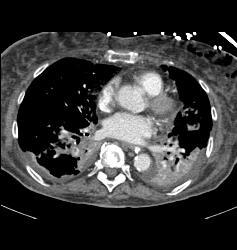

Diagnosis

Multiple Pulmonary Emboli (PEs)